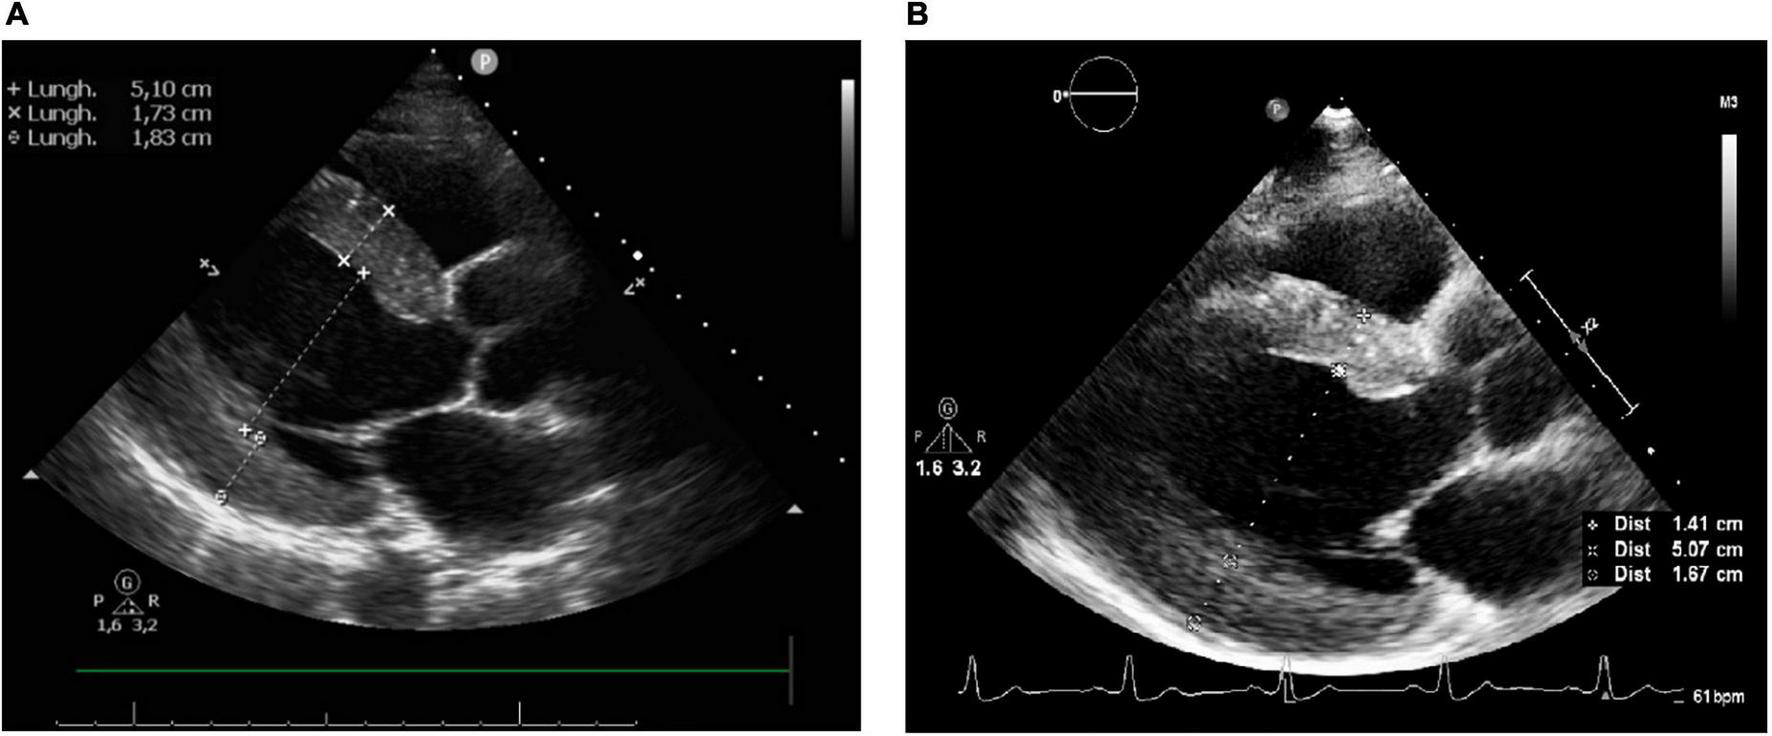

An echocardiogram (performed 4 months after the admission) showed absence of wall motion abnormalities, normal LVEF (65%) and significant reduction of LVH (LV mass index 67.8 g/m2.7, IVS and PW thicknesses 14.1 and 16.7 mm, respectively), left atrial dilatation and slight increase of ascending aorta diameter (Figures 5A,B).

FIGURE 5

(A) Echocardiography after 2 months since the admission. (B) Echocardiography after 4 months since the admission.